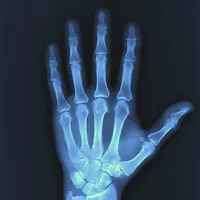

What are the three visibility components of every image?

Brightness, contrast, and noise

The three visibility components of every image are brightness, contrast, and noise. Brightness affects the lightness, contrast determines the difference between light and dark areas, and noise refers to unwanted variations in the image.

What is required for an image to be visible within your field of view?

Differing shades of brightness and darkness

For an image to be visible, it needs differing shades of brightness and darkness. This contrast allows our eyes to perceive shapes and details, making the image recognizable.